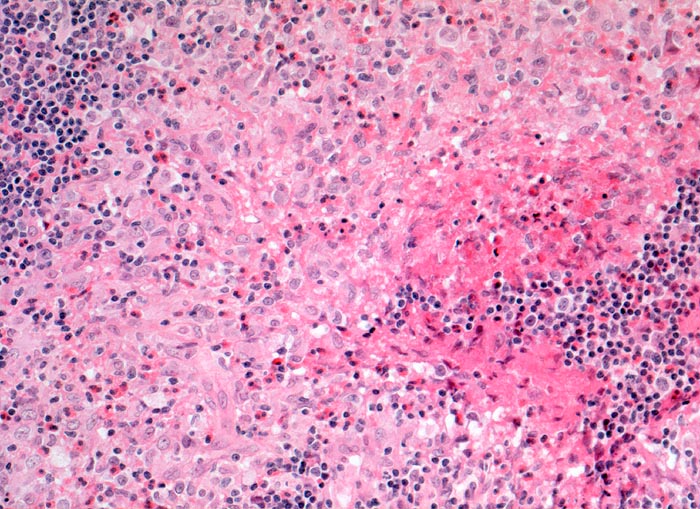

Langerhanszell Histiozytose

Lymphknoten, Kopf-cervikal

Infiltratherd bestehend aus Langerhanszellen mit bohneförmigen Kernen und reichlich hellem Zytoplasma. Dazwischen zahlreiche eosinophile Granulozyten.

CD1a und S-100 positive Langerhanszellen in den hellen Infiltratherden